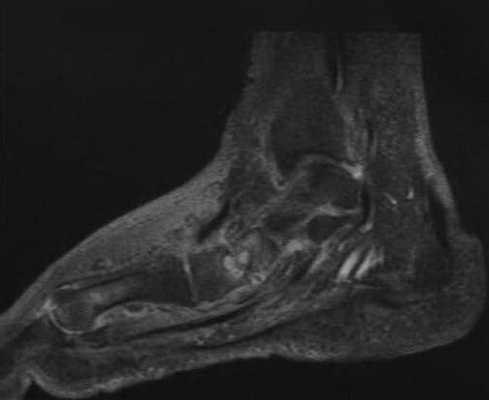

b) Т1 -взвешенная МРТ после введения контрастного вещества демонстрирует отек мягких тканей и отечные предплюсневые кости, так же как кистозные изменения и явления синовита.

(Справа) Рентгенография в боковой проекции, этот же пациент два месяца спустя: визуализируется прогрессирующая деструкция в зоне таранно-ладьевидного сустава. Произошла миграция дебриса, ограниченного растянутой капсулой, в тыльном направлении к таранной кости. Это типичный пример поражения сустава при нейропатической остеоартропатии (Шарко). (Слева) МРТ, сагиттальная проекция, режим Т1 с подавлением сигнала от жира, с контрастным усилением: визуализируются скопления жидкости при стопе Шарко (некоторые с дебрисом) вокруг голеностопною сустава и патологический сигнал от дистальною отдела большеберцовой кости. Металлический артефакт замутняет под таранный, таранно- ладьевидный и пяточно-кубовидный суставы.

(Справа) МРТ, аксиальная проекция, режим Т1, с контрастным усилением, с подавлением сигнала от жира: у этого же пациента визуализируются скопления жидкости в мягких тканях и сухожильных влагалищах. Это нейропатические скопления жидкости. Накопление контрастного вещества костной тканью связано с реактивными изменениями. Признаков инфекции при биопсии не обнаружено.